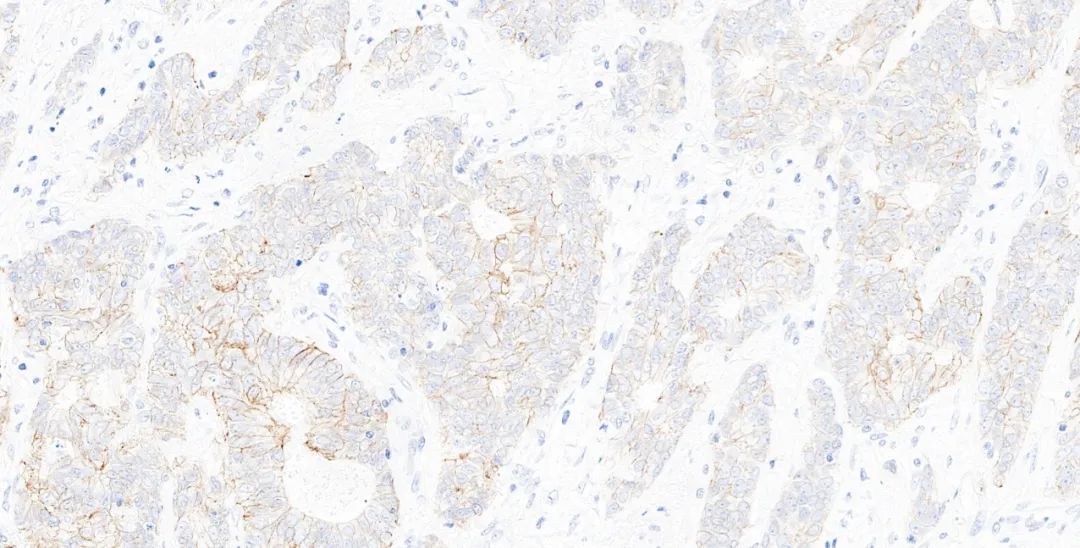

图4.基因科技免疫组化测评结果图:HER2(GT2245) 乳腺癌1-2+

图5.基因科技免疫组化测评结果图:HER2(GT2245) 乳腺癌3+